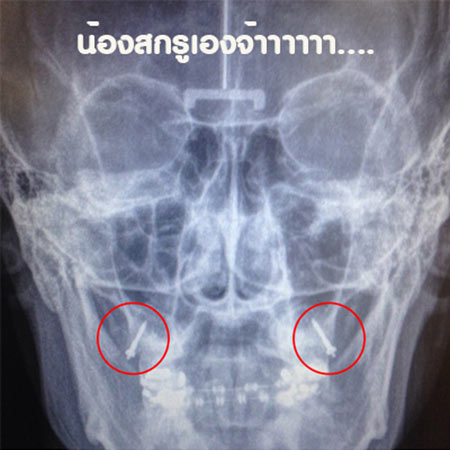

หลังจากนั้นไม่นานฟันของเธอก็เริ่มเข้าที่มากขึ้น แต่ยังติดปัญหาเรื่องกรามล็อก จึงทำให้เธอต้องใส่เครื่องมือพิเศษอีกครั้ง จนเวลาล่วงเลยเข้าสู่ปี 4 เนื่องจากช่วงนี้เธอต้องเรียนหนักมาก ทำให้ไม่มีเวลาไปหาหมอ เธอเริ่มมีปัญหาฟันผุ ต้องถอดเครื่องมือแล้วรักษาฟันใหม่ โดยครั้งนี้คุณหมอได้ขันสกรูเข้าไปยึดไว้ด้านในที่เหงือกข้างในสุดทั้งสองข้าง และเธอก็ได้พยายามดูแลสุขภาพช่องปากให้สะอาดมากขึ้น สุดท้ายฟันของเธอค่อย ๆ เรียงตัวและเข้าที่ในที่สุด